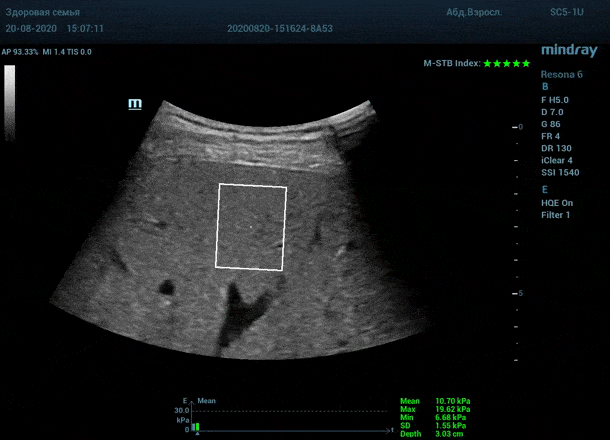

Как работает эластография сдвиговой волны? Датчик посылает плотный пучок ультразвуковых волн в ткани, ткани сжимаются, а затем возвращаются в исходное состояние за счет своей эластичности. Расправление ткани создают поперечные ультразвуковые волны, которые регистрируются трансдьюссером. Прибор во время исследования непрерывно отображает график значений плотности печени (kPa) в исследуемой зоне, достоверным считается график в виде прямой линии. Такая линия формируется путем получения близких по значению показателей. Количественным показателем является отношение межквартального интервала к медиане (IQR/Med). Допустимым считается результат с IQR/Med менее 30%. Чем данный показатель меньше, тем более точным является исследование. Для достоверного исследования в идеале нужно 10 значений.

3. - Неподвижная печень. Достигается путем задержки дыхания на выдохе. Выдох позволяет уменьшить давление на печень органами грудной клетки и брюшной полости. Задержка дыхания останавливает её. Критерием качества является индекс M-STB, выраженным в количестве звезд. Прибор определяет его автоматически. 4-5 звезд индекса свидетельствует о неподвижной печени.

Приводим видео пример: использованы 3 точки доступа печени, каждое значение графика получено прицельным выстрелом HQ Elasto и собрано в единый тренд. В результате анализа 10 значений получен удивительно точный результат - статистический разброс  3.5 % IQR/Med.